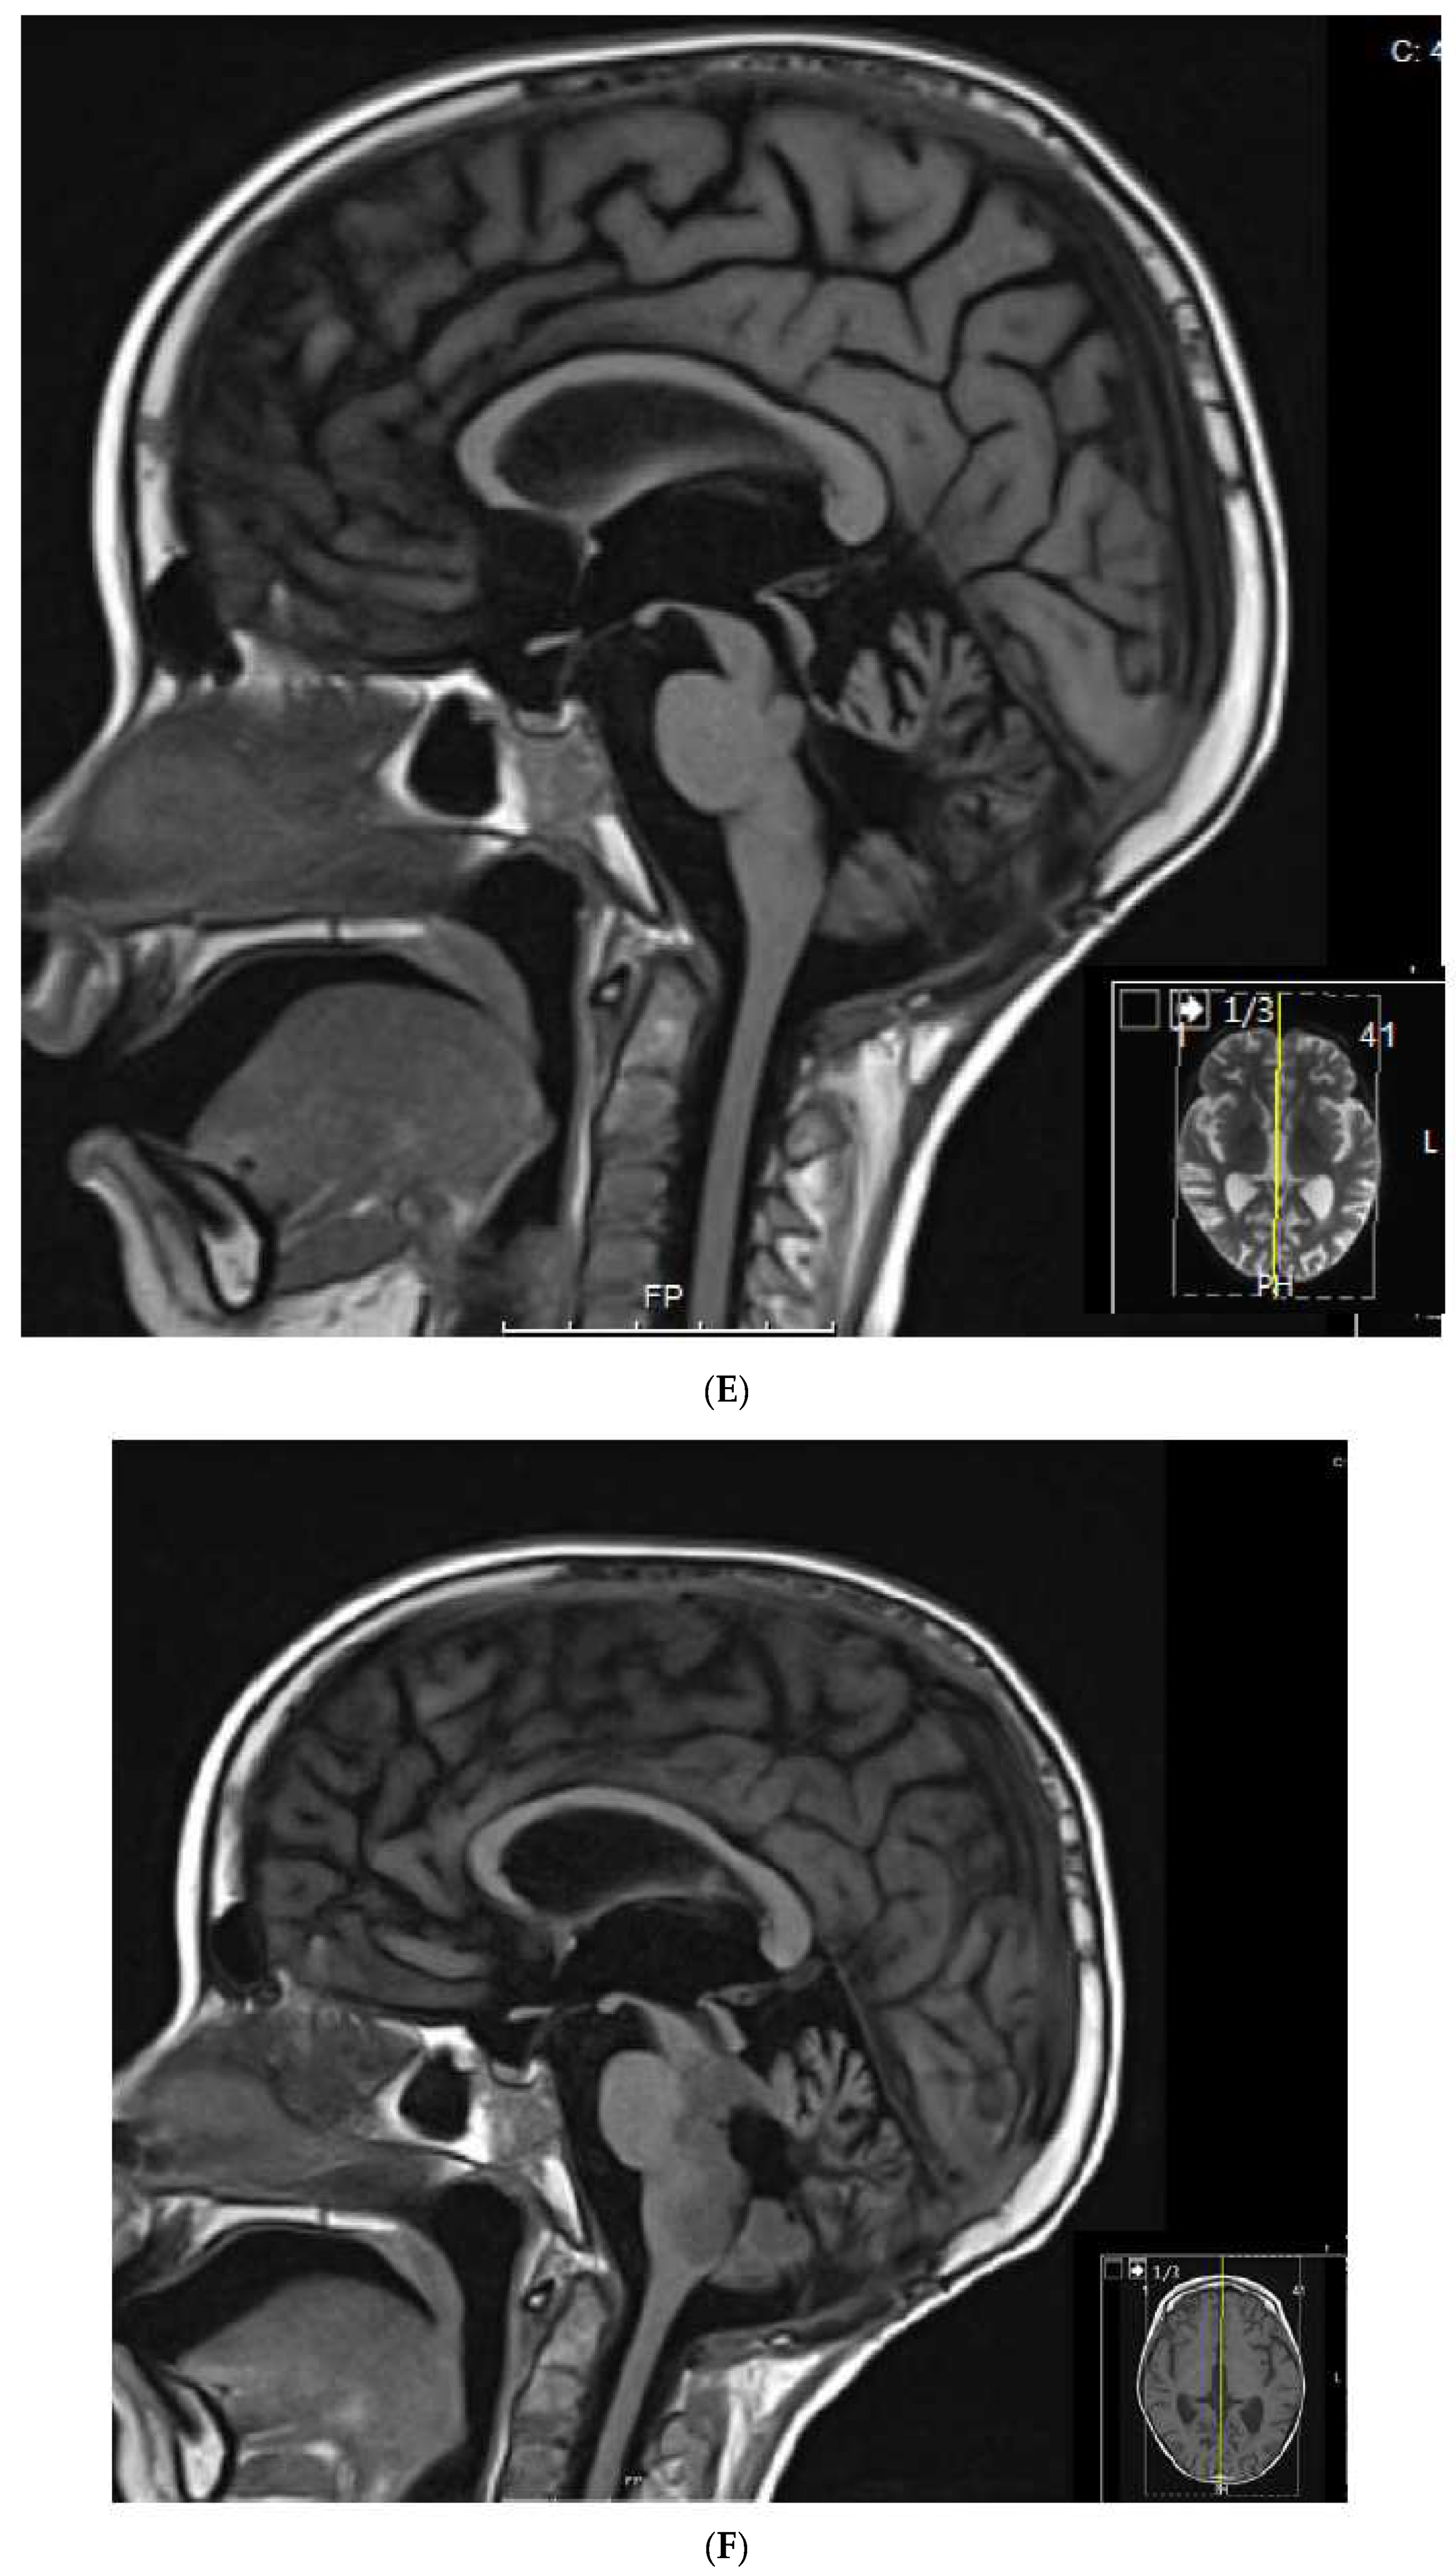

1.3. Patient 3

| 3 | Medulloblastoma Infratentorial Microscopic leptomeningeal relapse | VP16 alone (VA added later) | 10 months | CR | CR 5 years at last encounter Alive 7 years at last encounter |